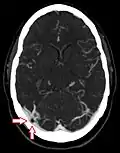

CT angiography showing an arachnoid granulation in the right transverse sinus -

Non-contrast CT scan of the head showing an arachnoid granulation